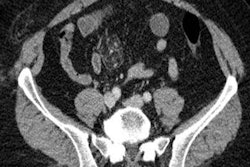

A team led by Dr. Rosanne Naunheim from the Washington University Barnes-Jewish Hospital in St. Louis compared 64 patients referred for head CT scans following the traditional referral pathway with use of the BrainScope One referral guideline. The researchers found that using the BrainScope One device could have led to a 33% reduction in head CT scanning in this patient group without any false-negative cases.